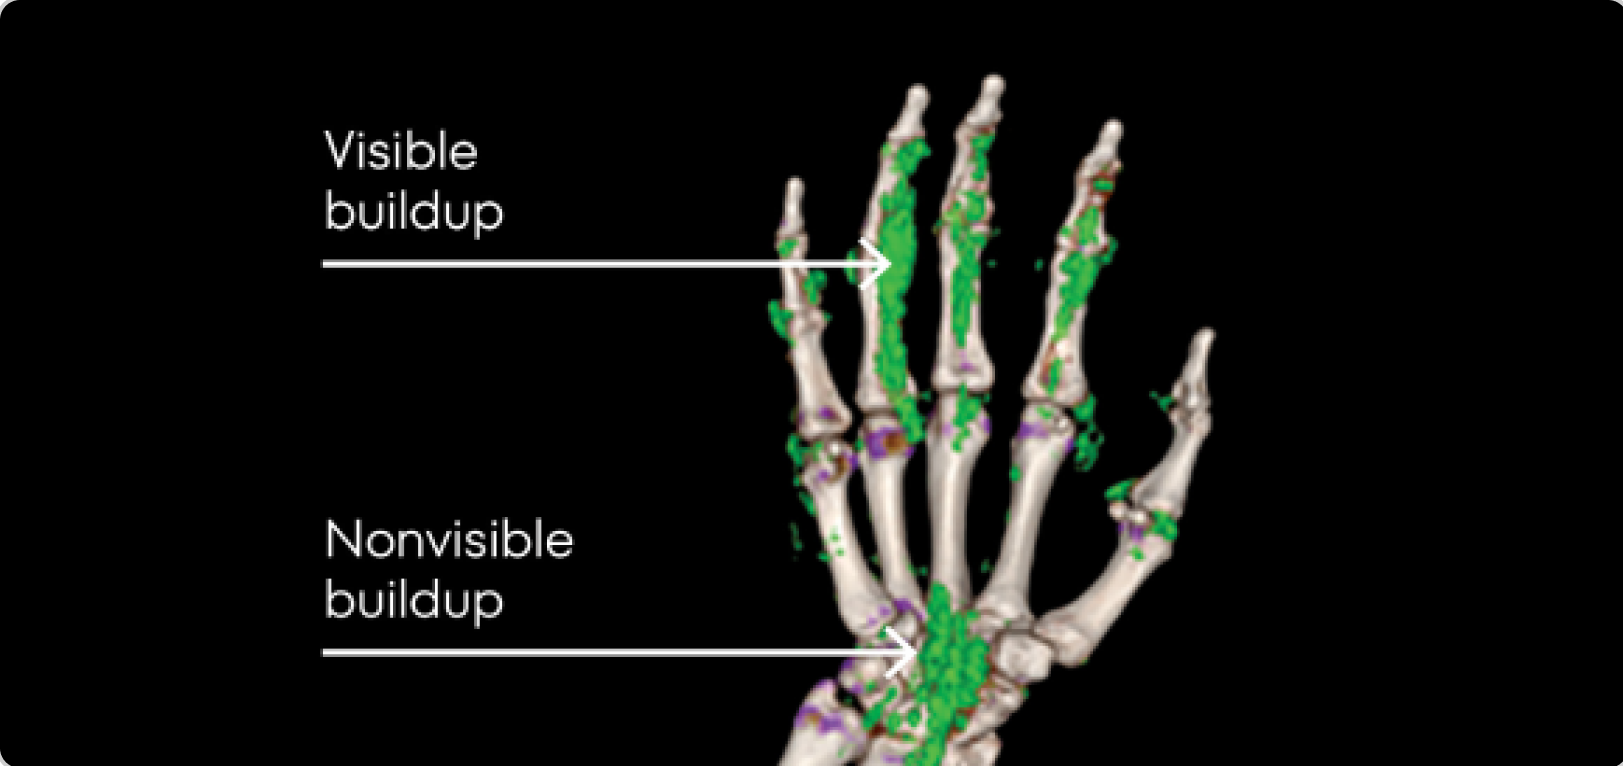

Image of tophi in hands with both visible and nonvisible buildup

PHOTO OF TOPHI BUILDUP

Image courtesy of Dr Jürgen Rech.

KRYSTEXXA is not indicated for the treatment of pain.

Dual Energy CT scan of hand showing visible and nonvisible buildup in gout patient

DECT OF URATE BUILDUP

DECT image courtesy of Dr Jürgen Rech. Green areas indicate urate crystal buildup.

DECT, dual-energy computed tomography.

KRYSTEXXA is not indicated for treatment of pain.